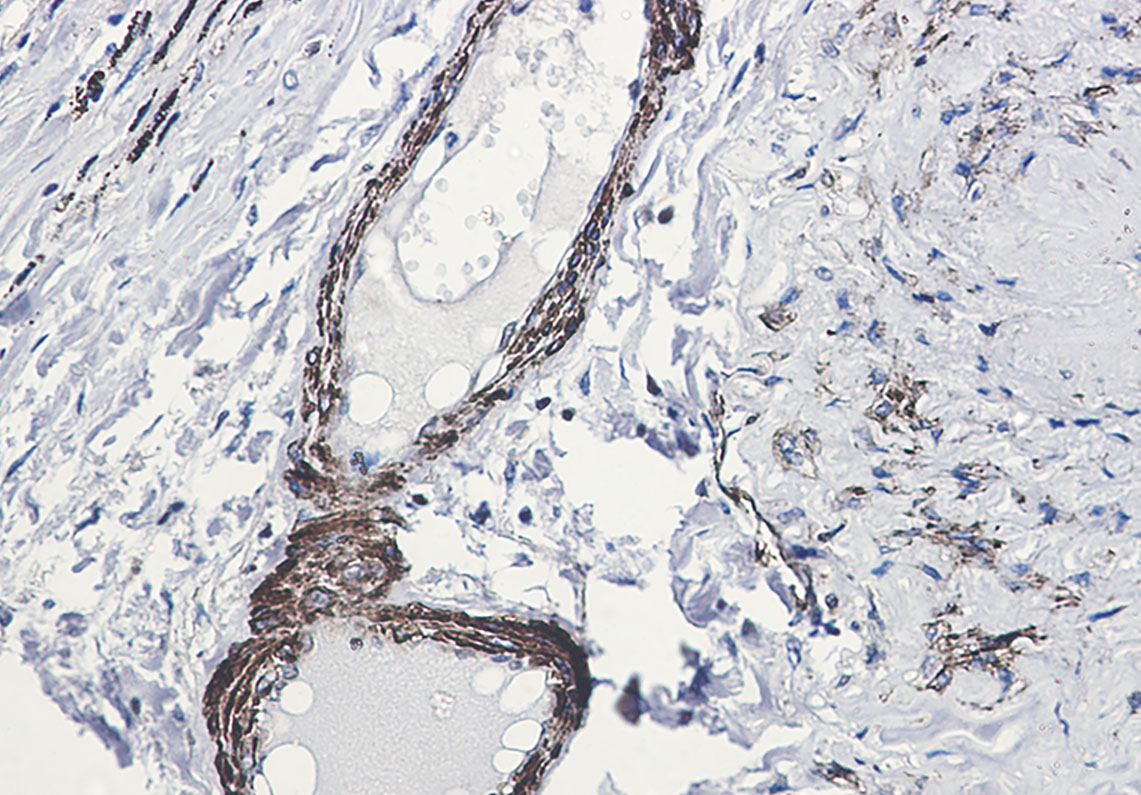

| Dilution | WB~~1/500-1/1000 IHC-P~~1:50~200 IP~~N/A |